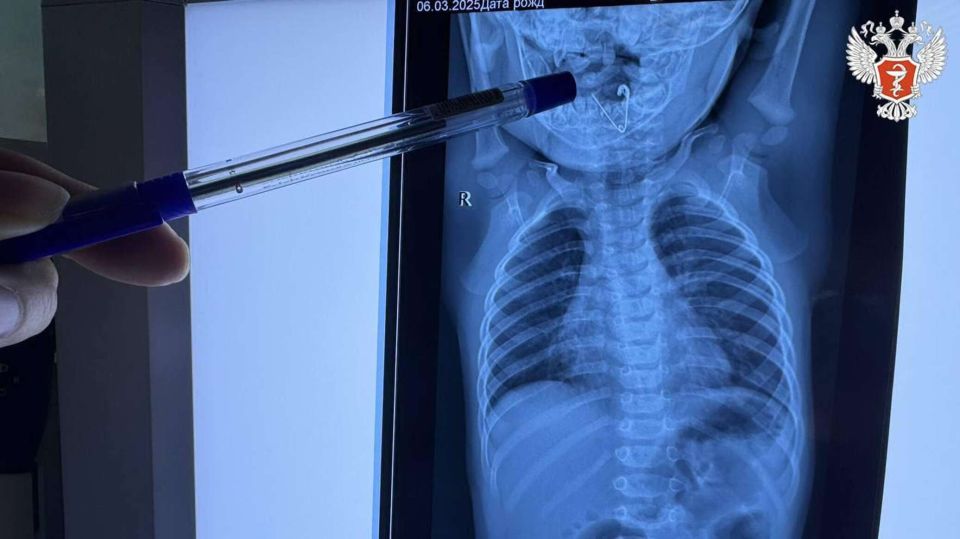

СИМФЕРОПОЛЬ, 1 ноя - РИА Новости Крым. Семимесячного ребенка, который проглотил раскрытую булавку, спасли врачи Приморского края. Об этом сообщает пресс-служба Минздрава России.Как рассказали в ведомстве, мама малыша накрыла его пледом, но забыла, что...